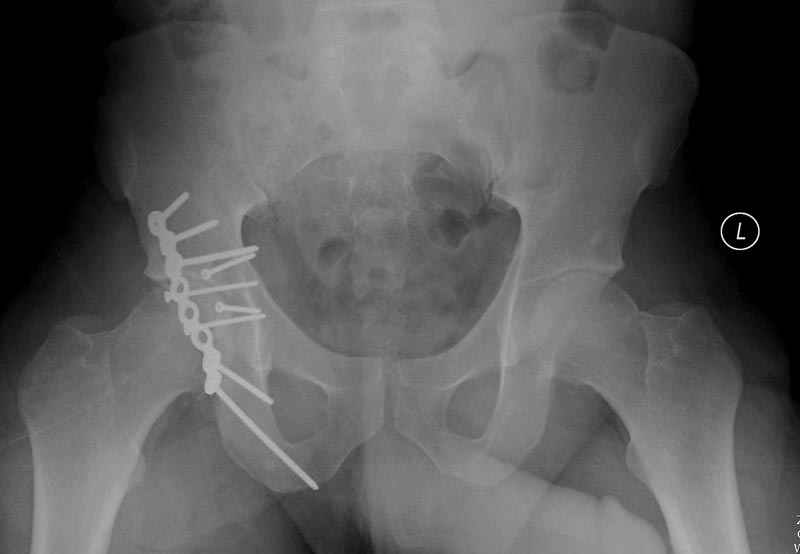

5:24 Рентгенограмма таза, вызывают врача ортопеда (снимок N1), его диагноз: закрытый переломо-вывих правого тазабедренного сустава, получает добро на закрытую репозицию в приемном отделении

5:38 Дважды неудачная попытка закрытой репозиции в приемном отделении

N 2

6:20 ответстенный врач принимает решение о репозиции в условиях операционной, предупреждаются родственники и больной, что при неудачной закрытой репозиции, о возможности открытой репозиции и фиксации задней стенки вертлужной впадины.

7:30 начало операции, больной на спине, попытка репозиции после анестезии N3, укладка больного на боку, доступ Kocher- Langenbeck, состояние седалищнего нерва около 2.5см кровоподтек, через joistick головка бедра приподнята, освобовождение сустава, фрагмент заднего края более 3х4 см репонирован на свое место. После промывания

сустава, репозиция вывиха (N4), фиксация фрагмента 2.7(4) мм шурупами и допольнительно реконструктивной пластиной на 8 дырок, фиксация 3.5мм шурупами проксимально и дистально.

Интраоперционные N5 косая запирательная и N6 подвздошный снимок

11:50 больной в послеоперационной, рентгенограмма N7, компьютерная томограмма в тот же день N8-10